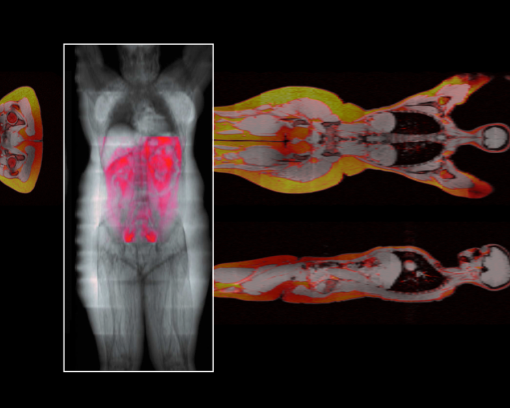

Investigating adipose tissue using fat-water magnetic resonance imaging (FW-MRI).

Imaging in Obesity

Signals from the brain and from other organs throughout the body drive healthy eating behavior. Changes in the balance of these systems contribute to the obesity epidemic. However, little is known about imbalances in functional brain networks in obesity. While homeostatic control of feeding behavior is largely regulated by the hypothalamus, distributed brain networks are increasingly recognized as potent non-homeostatic modulators of eating habits. Non-homeostatic modulators include palatability/reward, stress, motivation, and the balance between emotional drive and cognitive control.

Because lifestyle intervention in adults does not lead to long-lasting weight loss, and co-morbidities such as diabetes and cardiovascular disease develop over many years, the Niswender lab seeks a thorough understanding of the interaction of metabolic signals from the brain with behavior, the neurobiology of metabolism, and imaging in obesity.

Although the association of obesity, altered metabolism, and diabetes is well established in adults, we have little information about these associations during childhood and their relationships to future diabetes as these children become adults. Specifically, we do not understand the interaction of brain function, eating behavior, and obesity during childhood. Our research examines brain network function in children who are healthy weight or obese to discover differences in brain networks. These differences can then be targeted for the treatment, early intervention, and, ultimately, prevention of obesity.